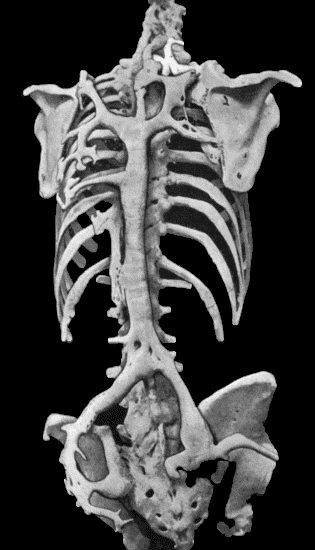

133.Skeleton of Rickety Dwarf 470

134.Changes in the Skull resulting from Ostitis Deformans 474

135.Cadaver, illustrating the alterations in the Lower Limbs resulting from Ostitis Deformans 475